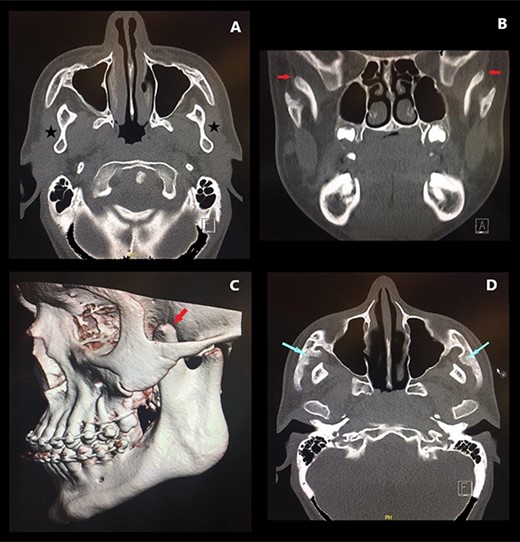

Preoperative CT ((A and D) axial sections, (B) coronal section, (C) 3D reconstruction) demonstrating CPH (red arrows), concavity of the ramus (stars) and bony deposits on the medial aspect of zygomatic arches (blue arrows).

On examination, the patient’s maximal inter-incisal distance was only 8 mm (Fig. 1). A CT scan confirmed marked coronoid hyperplasia bilaterally, and the thickened anterior borders of the rami created concave surfaces on the superolateral aspect of the mandible (Fig. 2A). The condyles appeared hypoplastic although otherwise fully functional and non-ankylosed, and the superior aspect of the coronoid processes deviated laterally, curving over the superior aspect of the zygomatic arch on both sides. (Fig. 2B and C). In addition, exophytic bone deposits had formed on the medial aspect of the zygomatic arches suggestive of either benign exostosis or reactive hyperplasia (Fig. 2D).